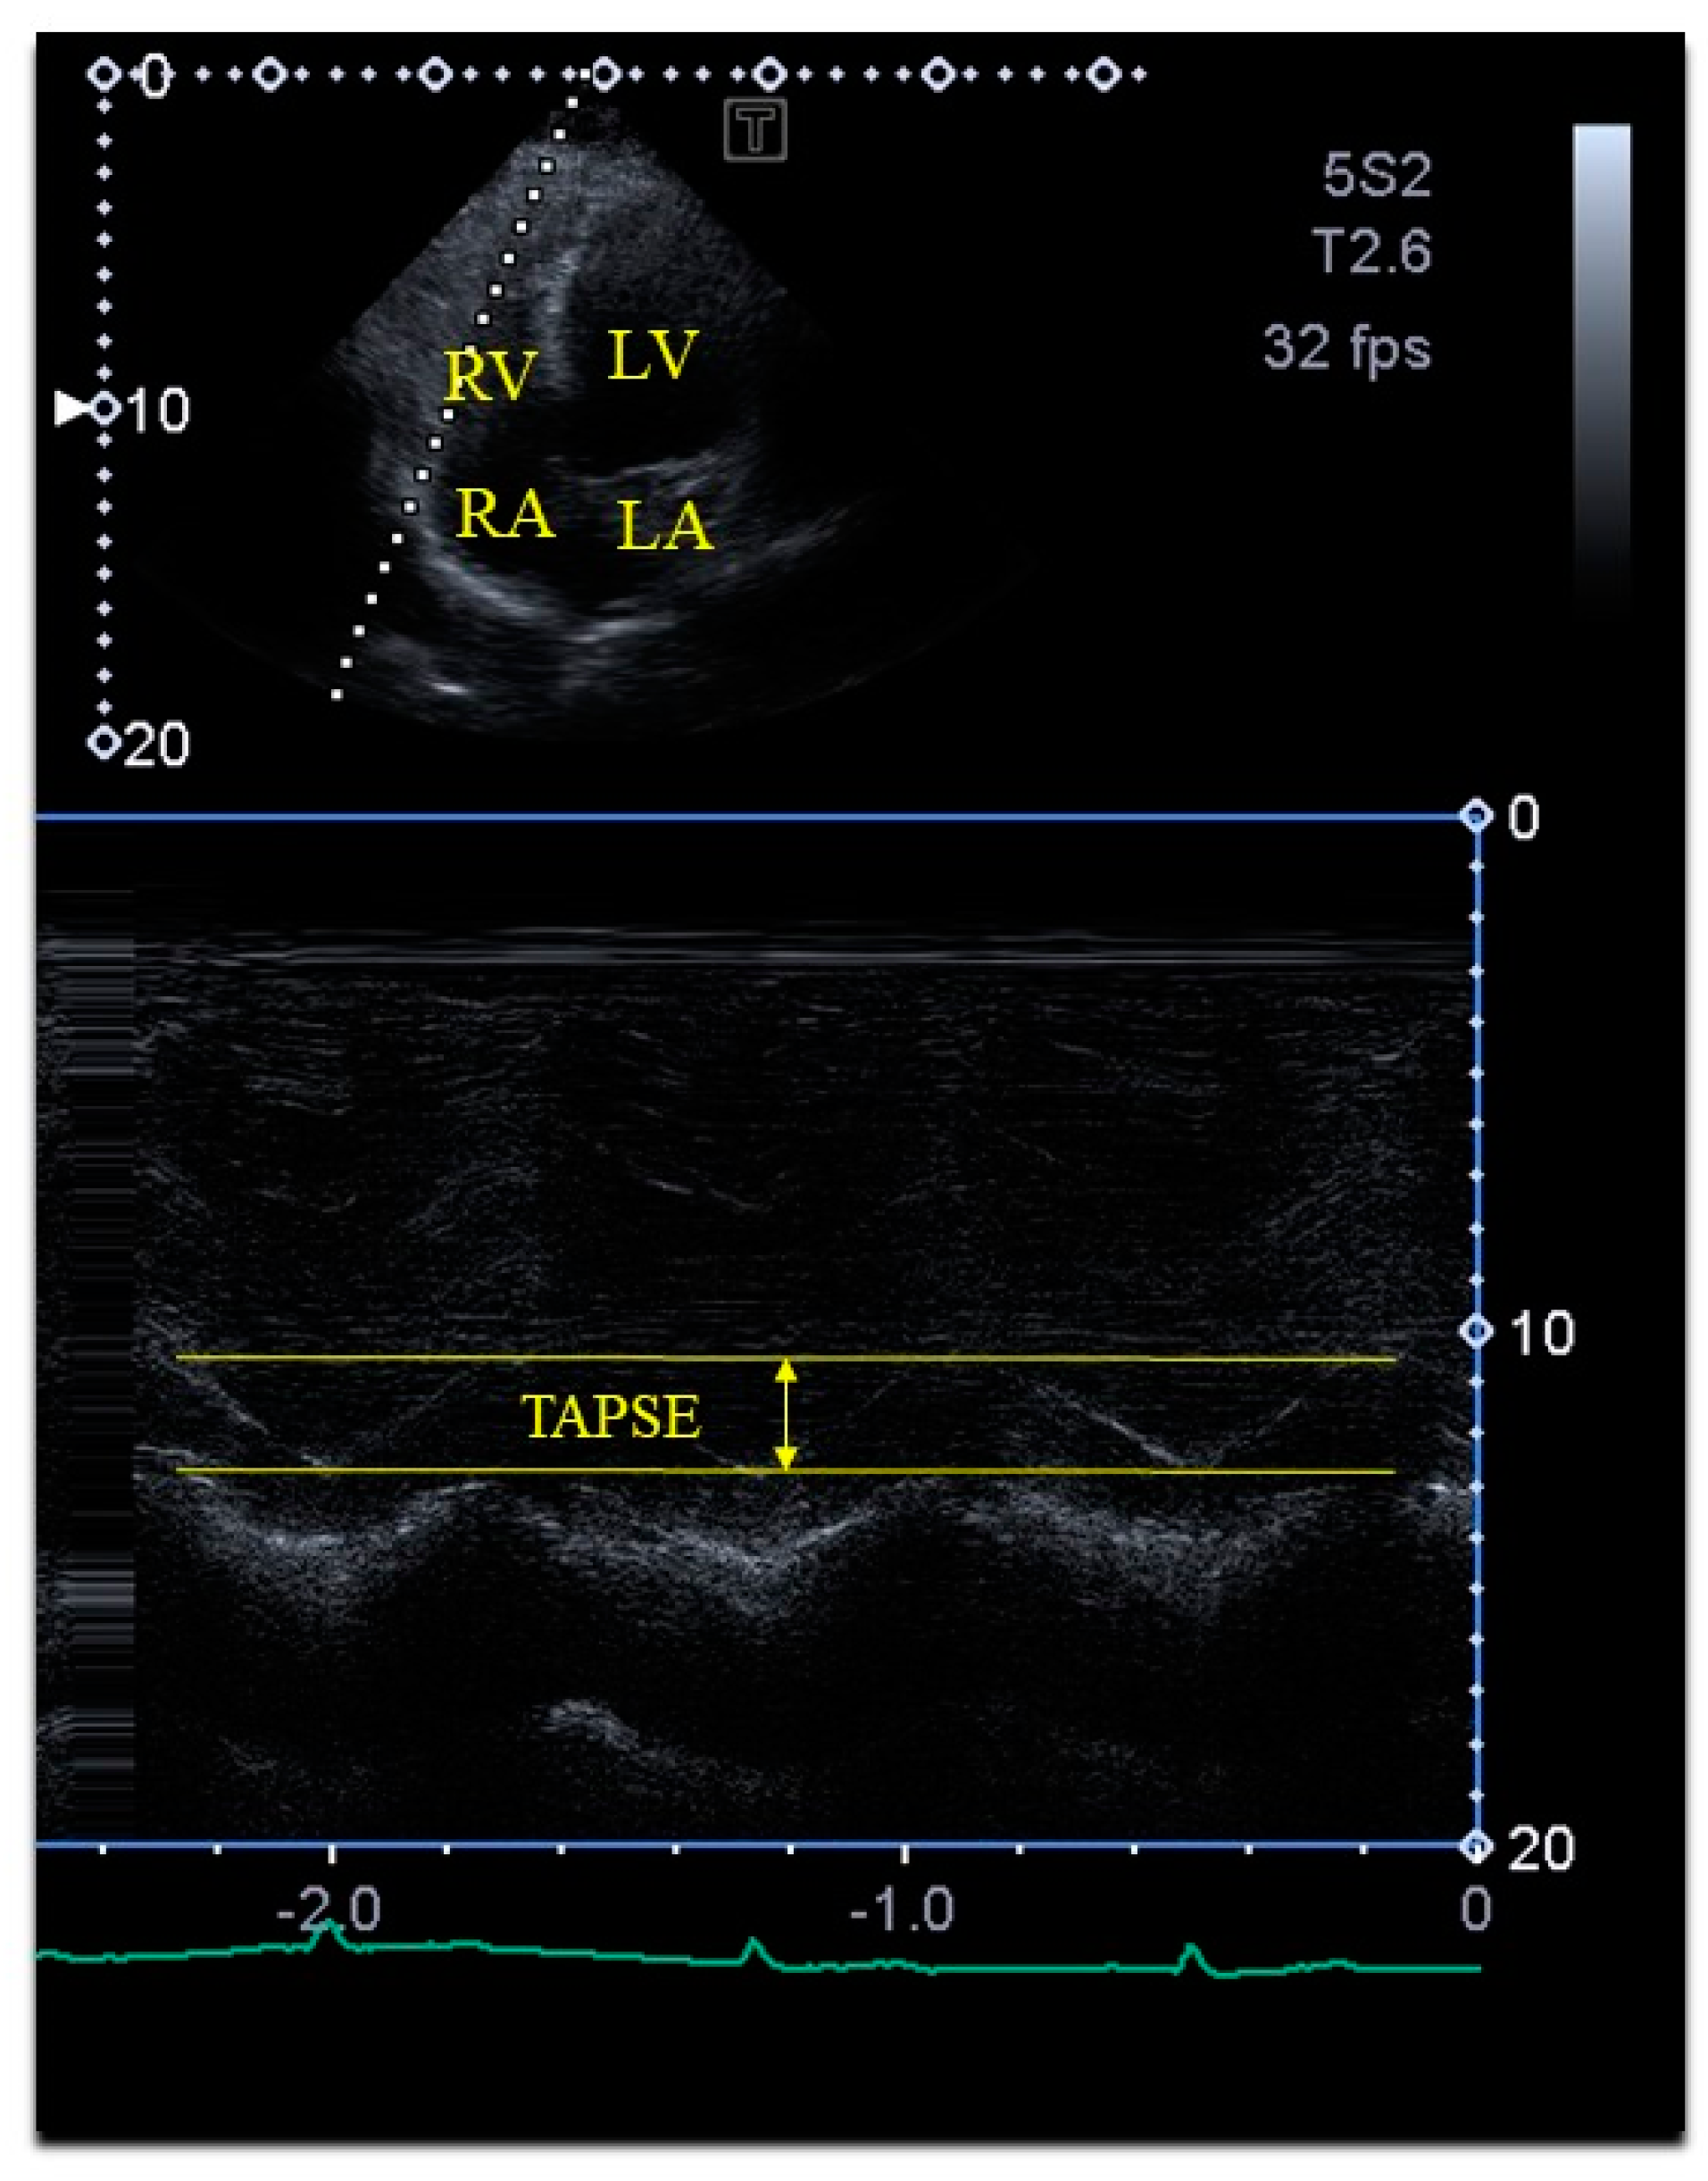

| Tricuspid annular plane systolic excursion (mm) | 23.7 ± 2.9 |